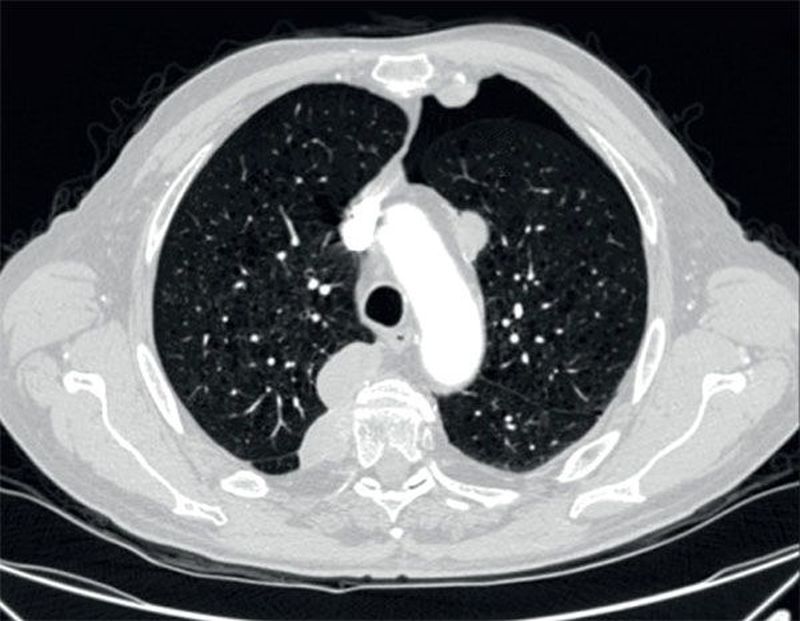

A 71-year-old man with known lung metastases from renal cell carcinoma under cabozantinib therapy presented with worsening of dyspnoea. The CT scan revealed a left apical pneumothorax. What was the cause of the pneumothorax? A)Progression of the lung metastases B)A rapid and significant shrinkage of the lung lesions C)Spontaneous rupture of air blisters D)Severe interstitial lung disease due to cabozantinib